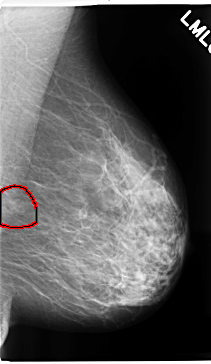

C_0259_1.LEFT_MLO

LEFT_MLO LINES 4720 PIXELS_PER_LINE 2736 BITS_PER_PIXEL 12 RESOLUTION 50 OVERLAY

FILE: C_0259_1.LEFT_MLO.OVERLAY

TOTAL_ABNORMALITIES 1

ABNORMALITY 1

LESION_TYPE MASS SHAPE OVAL MARGINS ILL_DEFINED

ASSESSMENT 4

SUBTLETY 3

PATHOLOGY BENIGN

TOTAL_OUTLINES 1

BOUNDARY